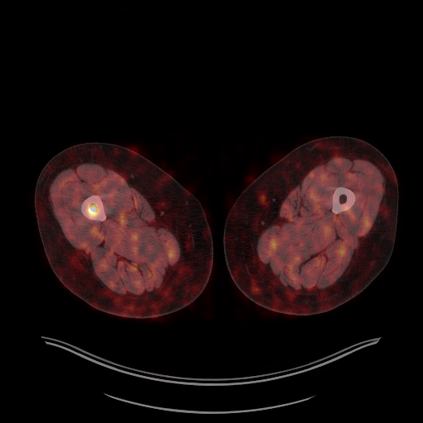

Medical images play a crucial role in assisting diagnosis, remote consultation, and academic research. However, during the transmission and sharing process, they face serious risks of copyright ownership and content tampering. Therefore, protecting medical images is of great importance. As an effective means of image copyright protection, zero-watermarking technology focuses on constructing watermarks without modifying the original carrier by extracting its stable features, which provides an ideal approach for protecting medical images. This paper aims to propose a fragile zero-watermarking model based on dual quaternion matrix decomposition, which utilizes the operational relationship between the standard part and the dual part of dual quaternions to correlate the original carrier image with the watermark image, and generates zero-watermarking information based on the characteristics of dual quaternion matrix decomposition, ultimately achieving copyright protection and content tampering detection for medical images.